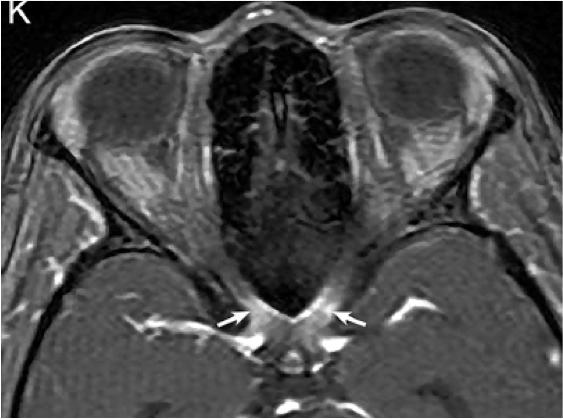

2. NMOSD 视神经MRI:病变较长,累及视交叉